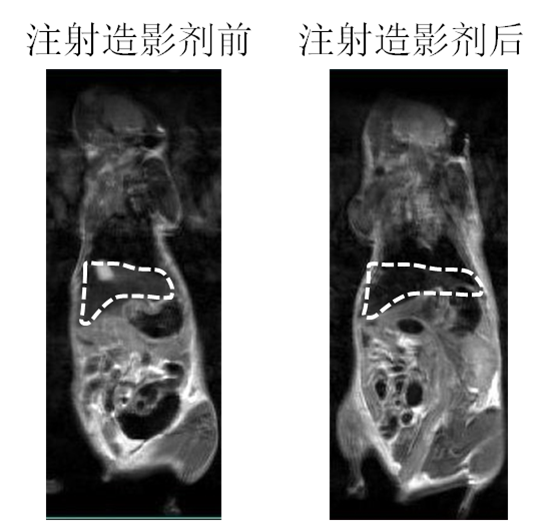

磁性纳米材料作为磁共振(MRI)造影剂的应用